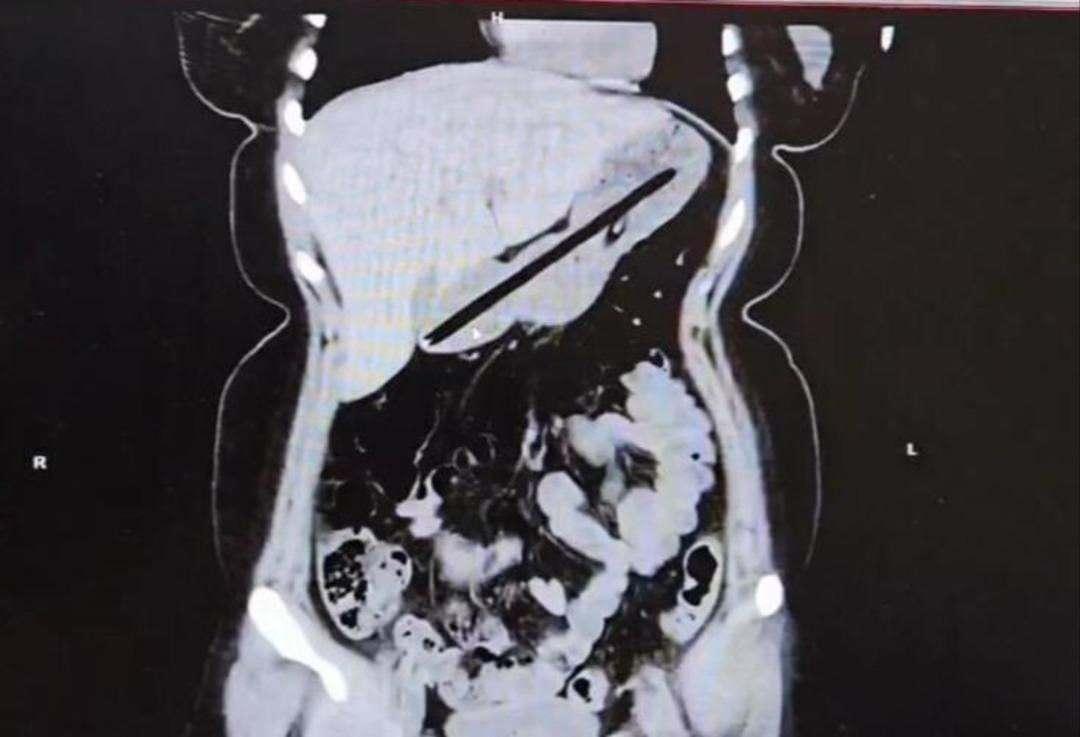

Ağrı’da obsesif kompulsif bozukluk (OKB) rahatsızlığı bulunan genç bir bayan, karın ağrısı ve mide rahatsızlığı şikayetleriyle hastaneye başvurdu. Şikayetlerinin akabinde yapılan endoskopi sonucunda tabipler şaşkınlık yaşadı.

Kadının midesinden biri kurşun, oburu ise tükenmez olmak üzere iki farklı kalem çıkarıldı. Sıhhat grupları olayla ilgili ayrıntılı inceleme başlatırken, bayanın ruhsal tedavisinin sürdüğü öğrenildi.

Operasyonu gerçekleştiren Dr. Öğretim Üyesi Adem Aslan, birinci defa bu türlü bir olayla karşılaştıklarını belirterek, “22 yaşındaki bayan hastamız kalem yutma şikayetiyle ilçe devlet hastanemize başvurmuştu. Tomografisinde midesinde yabancı cisim olduğu görüldü. Biz de tetkiklerimizde midesinde kalem olduğunu gözlemledik. Daha evvel toplu iğne, kemik kesimi üzere yabancı cisimlerle karşılaşıyorduk lakin bu kadar uzun ve ince bir cisim birinci kere karşımıza çıktı. Midenin boşalması için bir gün bekledik ve sonraki gün yaptığımız endoskopide hastanın bir değil iki kalem yuttuğunu gördük.” ifadelerinde bulundu.